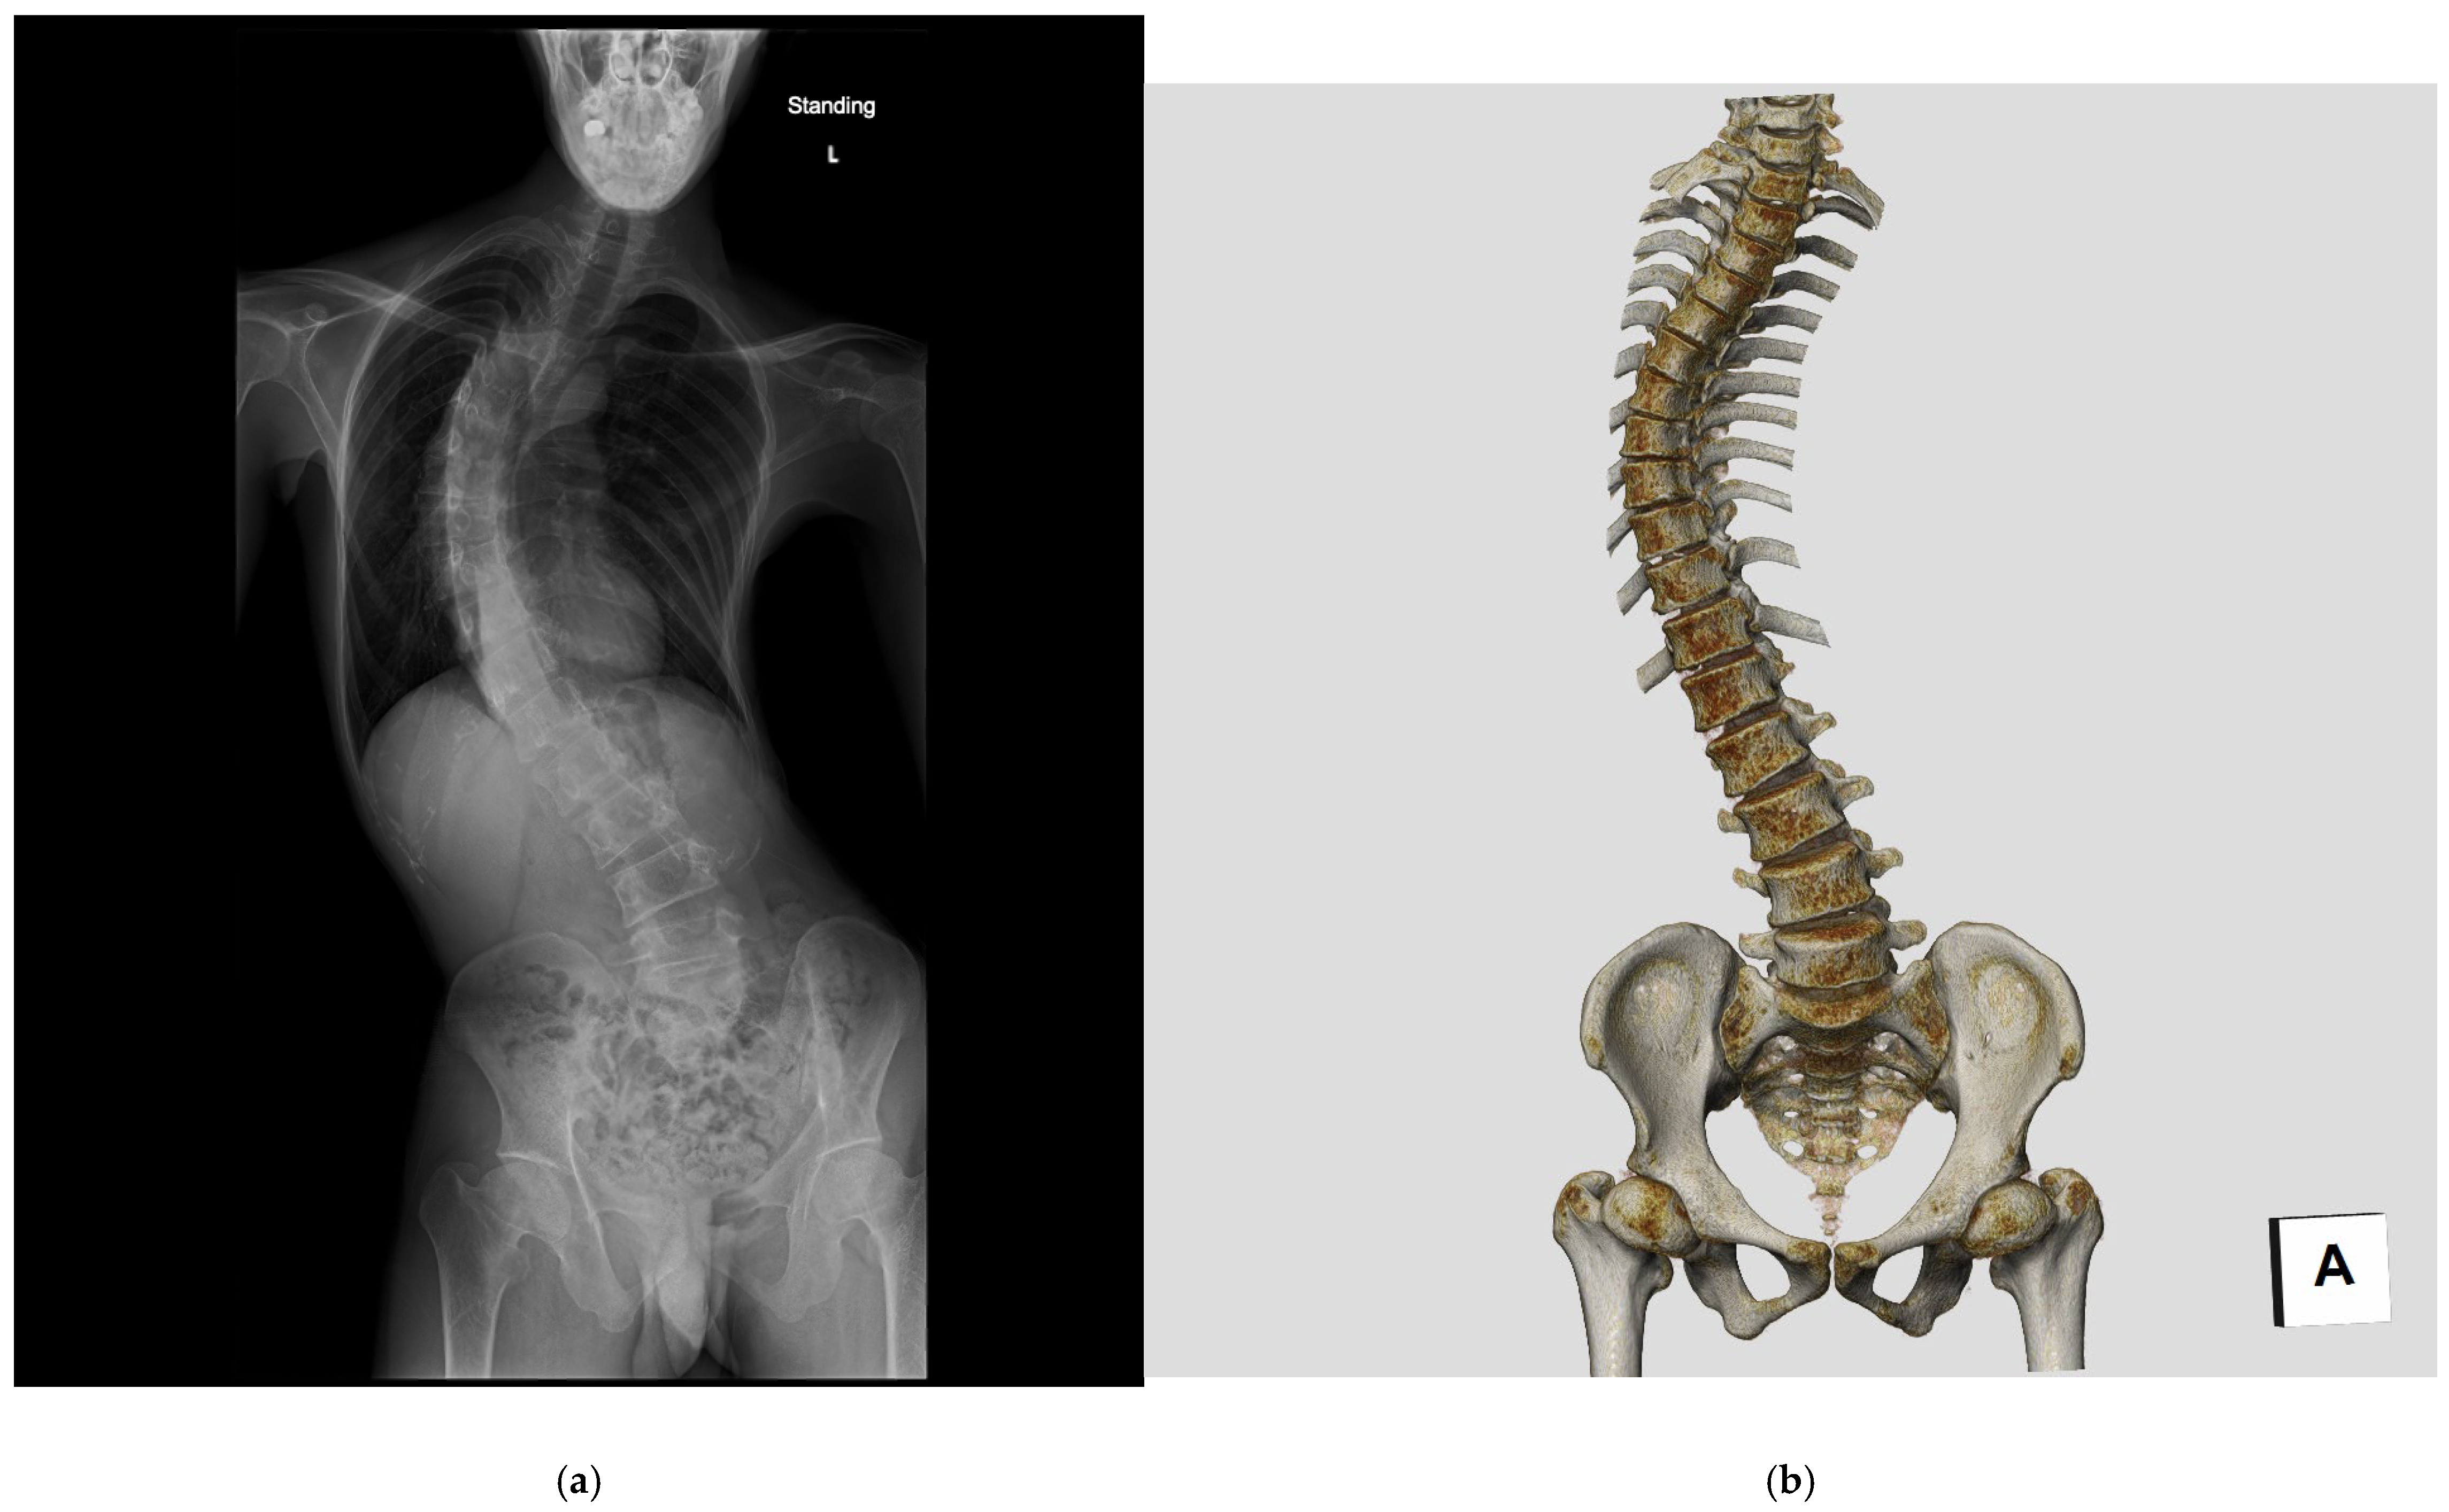

Scoliosis is a three-dimensional deformity of the spine that develops due to various etiological factors. (Figure 1). Adolescent idiopathic scoliosis (AIS), the most prevalent type of scoliosis, accounting for 80–90% of all cases, occurs during the growth period, particularly in the upper elementary to junior high school grades. The incidence of AIS is reportedly five to seven times higher in females than males, with a >90% incidence rate in identical twins [11]. Gradually, genetic predisposition to AIS is increasingly being studied; studies have pointed out a positive correlation between maternal scoliosis and the probability of developing scoliosis in children [12,13].

Figure 1. Radiographic and CT images of a patient with adolescent idiopathic scoliosis (AIS). (a) Standing postero-anterior (PA) radiograph of the whole spine. (b) Three-dimensional computed tomography (3DCT) image reconstructed using volume rendering.